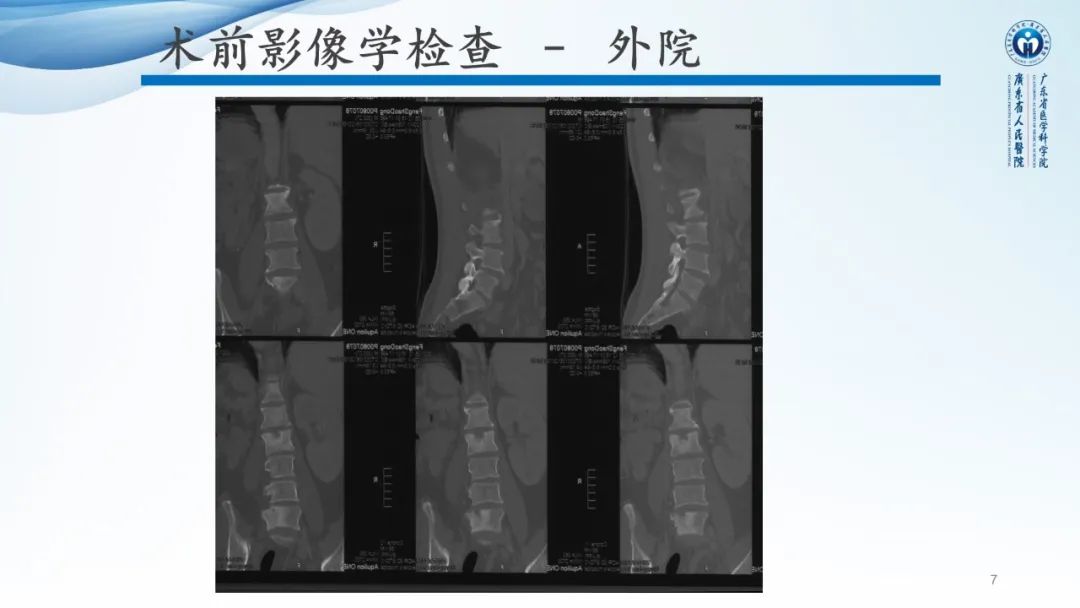

【病例】一例表现为弥漫中轴骨骨质增生硬化病变讨论-1